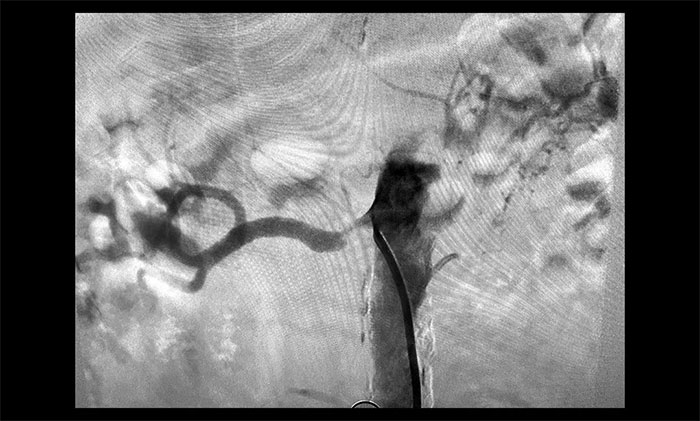

席剛明教授進一步行DSA腦血管造影檢查,患者腦動脈多發(fā)性狹窄(右側(cè)頸內(nèi)動脈、大腦中動脈、基底動脈等),左側(cè)頸總動脈閉塞,右側(cè)椎動脈閉塞,右側(cè)腎動脈重度狹窄(狹窄率大于70%),左側(cè)腎動脈閉塞。

▲ 患者右側(cè)腎動脈重度狹窄,左側(cè)閉塞